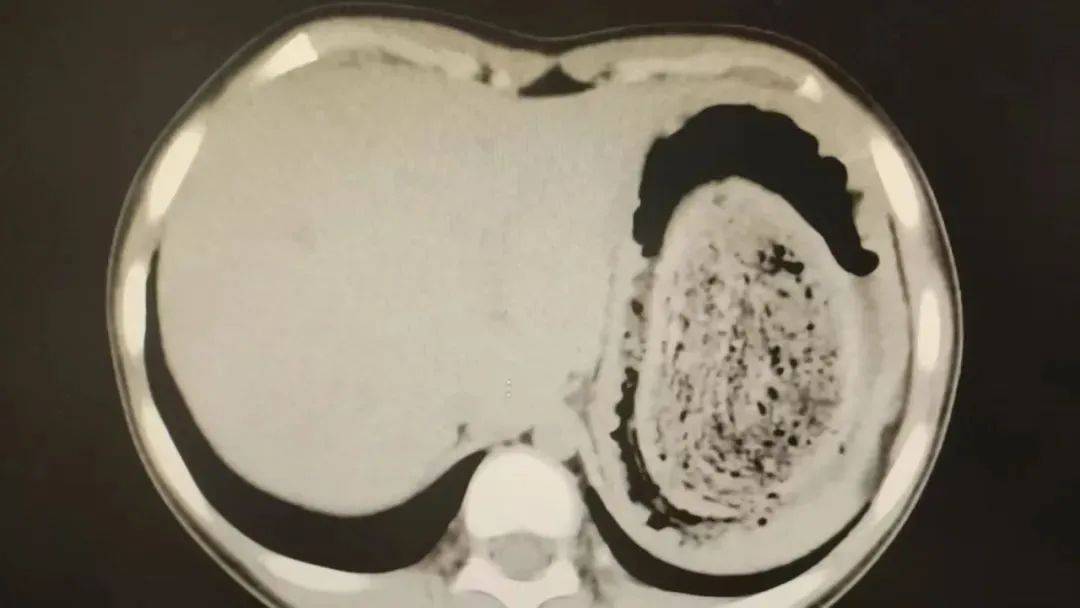

10岁女孩园园(化名)因持续3天的上腹痛伴呕吐被紧急送医皇冠登3管理出租 。影像学检查结果显示,她的胃部存在一个巨大的团块状阴影,初步怀疑为异物堵塞。据家长回忆,园园从1年前开始就有偷偷吃头发的习惯,但家人并未重视,直到这次症状严重才意识到问题的严重性。

在胃镜帮助下,妮妮胃里的情况逐渐明了皇冠登3管理出租 。一个滚圆黑色的毛发球混合着食物残渣占据整个胃腔,这些头发相互缠绕形成一个实心的“发石”,此外胃里还有一个鸡蛋大小的溃疡。

“发石”混杂着食物残渣,就像一个黑色的小西瓜皇冠登3管理出租 。由于整个“发石”体积太大,为避免损伤胃壁,医生借助手术工具将“发石”切割、分解,再小心翼翼地分块取出。整场手术持续2个多小时,最终取出4斤头发碎片。